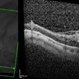

- vitreoschitic membrane

- vitreoschisis, myopic traction maculopathy

- Triamcinolone enhanced visualization of vitreoschisis membrane and removal in a case of myopic traction maculopathy.